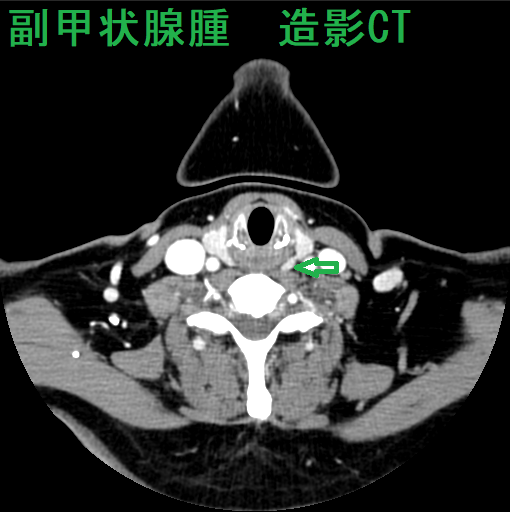

造影CTで副甲状腺腫瘍の位置を再確認します。

原発性副甲状腺機能亢進症手術症例の2.6-6.8%は、定位置にない異所性副甲状腺腫です。縦隔などエコーが届かない場所にある異所性副甲状腺腫に、造影CT, 99m-Tc MIBI-SPECTは有用です。